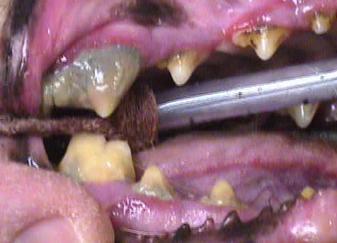

Calculus removal (Scaling)

Most pets have a large amount of tartar (calculus) present on their teeth from prolonged accumulation.  During a professional dental cleaning, an ultrasonic scaler is used to remove all of the tartar.  The calculus is removed from the surface of the tooth and also from the gingival pocket underneath the gum line.  It is only then that the teeth can be examined properly.

It is impossible to examine the teeth properly before all of the tarter is removed.  Each tooth will be examined with a dental probe to measure the depth of the gingival pocket around the tooth.  Each tooth is evaluated according to its own merit and a decision is made as to the outcome.  Our goal is to keep every tooth possible in the mouth, however, there are many reasons why a tooth may need to be extracted.  This may include periodontal disease, loss of tooth attachment, bone loss around the tooth, broken teeth, crowded teeth, retained baby teeth, or other painful tooth conditions.  We will make every effort to save marginal teeth though in some instances it may be best to have the tooth extracted.